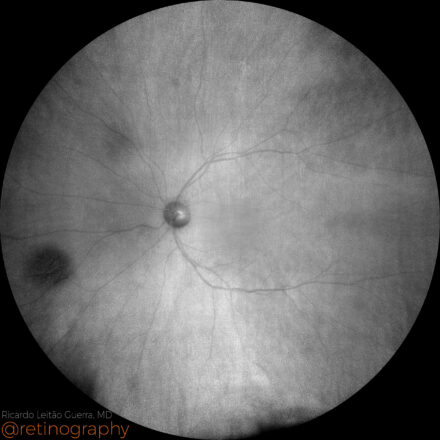

Choroidal nevus

57yo

57yo Choroidal nevus is best visualized using near-infrared reflectance (NIR) imaging. Its appearance may vary: it can be hyperreflective in confocal systems or hyporeflective in non-confocal imaging, depending on the imaging modality and melanin density. NIR enhances contrast for detecting and monitoring nevi, especially when they are not clearly visible on […]